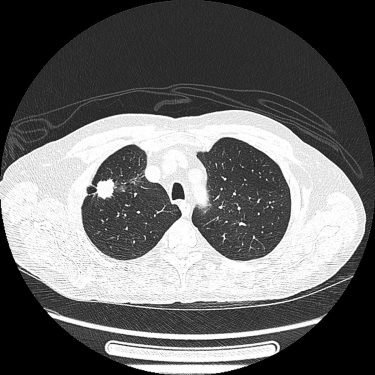

CT-Aufnahme eines bösartigen Lungentumors im Lungenoberlappen